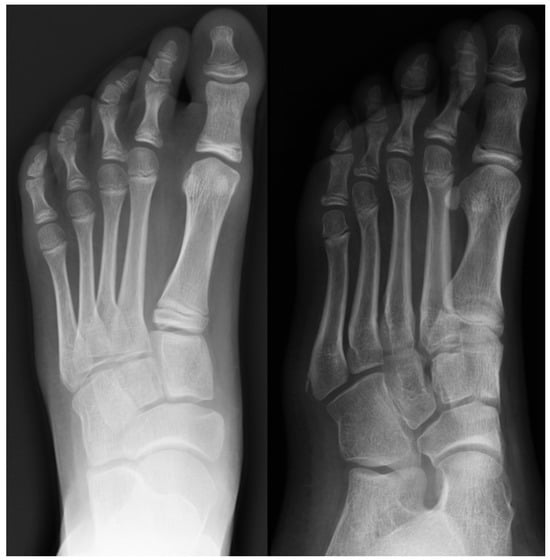

Radiograph (left) and MRI (right) of a 17-year-old female patient showing necrotic changes and initial flattening of the second metatarsal head.

Figure 11.

Radiograph (left) and MRI (right) of a 15-year-old male patient with osteochondrosis of the third metatarsal head and early signs of deformation.